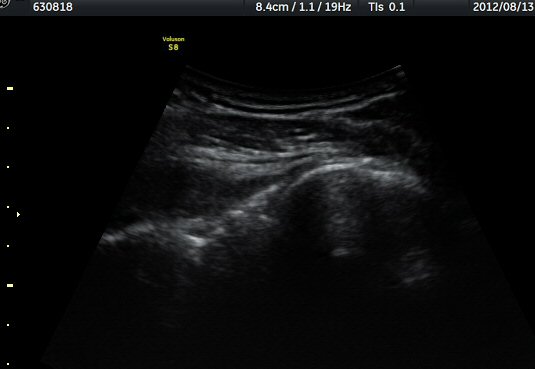

ÈíÀÎ 14ÀÏ ÈÄ ÃÊÀ½ÆÄ°Ë»ç¿¡¼­ ¾à°£ÀÇ ³¶Á¾ Å©±â °¨¼Ò°¡ °üÂûµÈ´Ù(±×¸² 7, 8)

ÈíÀÎ 50ÀÏ ÈÄ ÃÊÀ½ÆÄ°Ë»ç¿¡¼­ ³¶Á¾ Å©±â °¨¼Ò°¡ ¶Ñ·ÈÇÏ´Ù(±×¸² 9, 10).